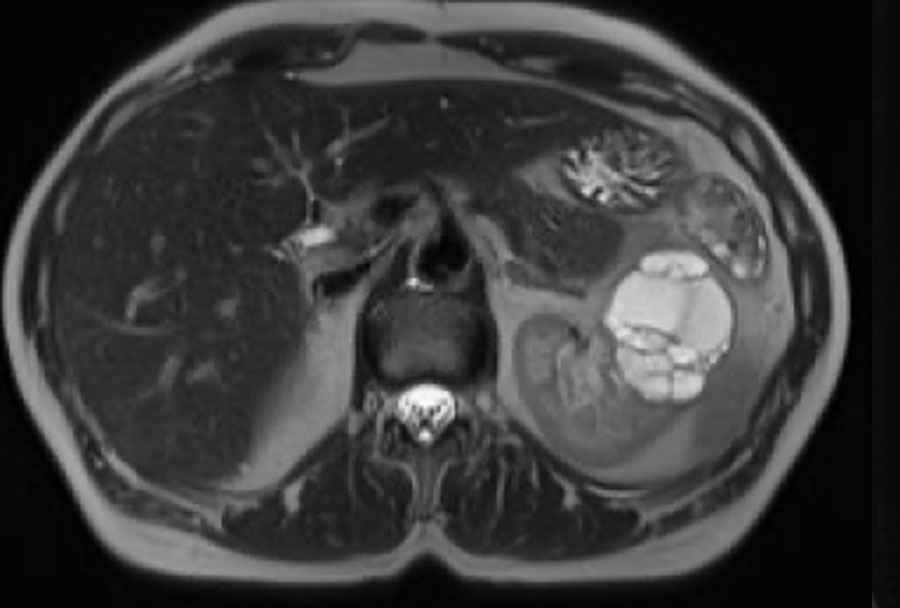

Ảnh T2W mặt phẳng axial và ảnh T1W mặt phẳng coronal có bão hòa mỡ và tiêm Gadolinium.

Có một khối dạng nang ở thận trái với nhiều vách ngăn mỏng ngấm thuốc.

Tổn thương được phân loại là Bosniak IIF.